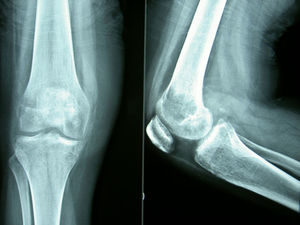

Pruebas complementarias. El estudio radiológico inicial mostró una radiolucencia difusa de la metáfisis y la epífisis femoral distal, sin líneas de fractura; el espacio articular permanecía normal (fig. 1). La resonancia magnética (RM) mostraba un extenso edema óseo en la epífisis femoral distal, más marcado en cóndilo externo, con disminución de la señal en T1 y aumento en T2, además de un pequeño derrame articular difuso (fig. 2).